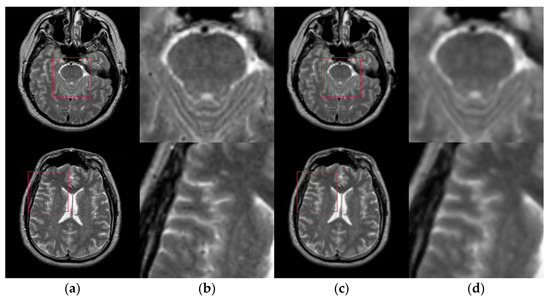

Figure 6 shows the results of two test images processed by the proposed hybrid spatial filter. It can be seen that the images after hybrid spatial filtering are smoother. The noise has been removed, and the details and structural information in original images are well preserved.

Figure 6.

An example of hybrid spatial filter. (a) Original images, (b) Part of the enlarged original images (c) The results obtained by hybrid spatial filter, (d) Part of the enlarged results images.